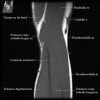

팔꿈치 관절의 MRI 단면 영상

1. Coronal section

1) Collateral ligament

2) Common extensor/flexor tendon group patholgy as well as epicondylitis